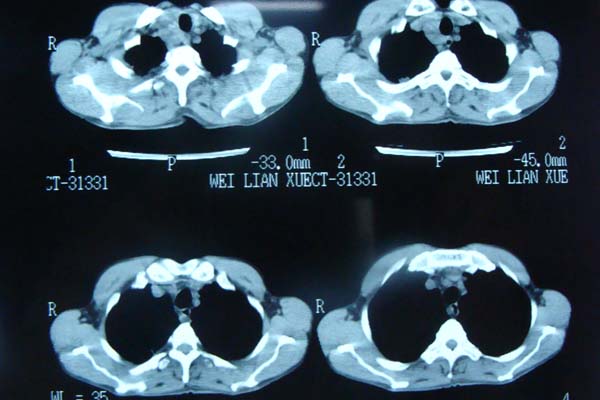

以下是引用pujunzhi在2009-6-21 21:48:00的发言:[br]右肺上叶后段见一空洞性病灶,灶周有渗出即晕征,右肺门肿大---可考虑感染性空洞和癌性空洞,先抗炎抗痨后复查并完善相关检查。有癌性空洞伴肺门淋巴结转移的可能。